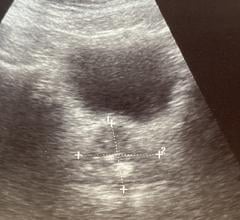

May 19, 2022 — Robert L. Bard, M.D., an ITN editorial advisory board member, received one of the highest achievements of ...

May 16, 2022 — The Barcelona Supercomputing Center (BSC) coordinates QUSTom (Quantitative Ultrasound Stochastic ...